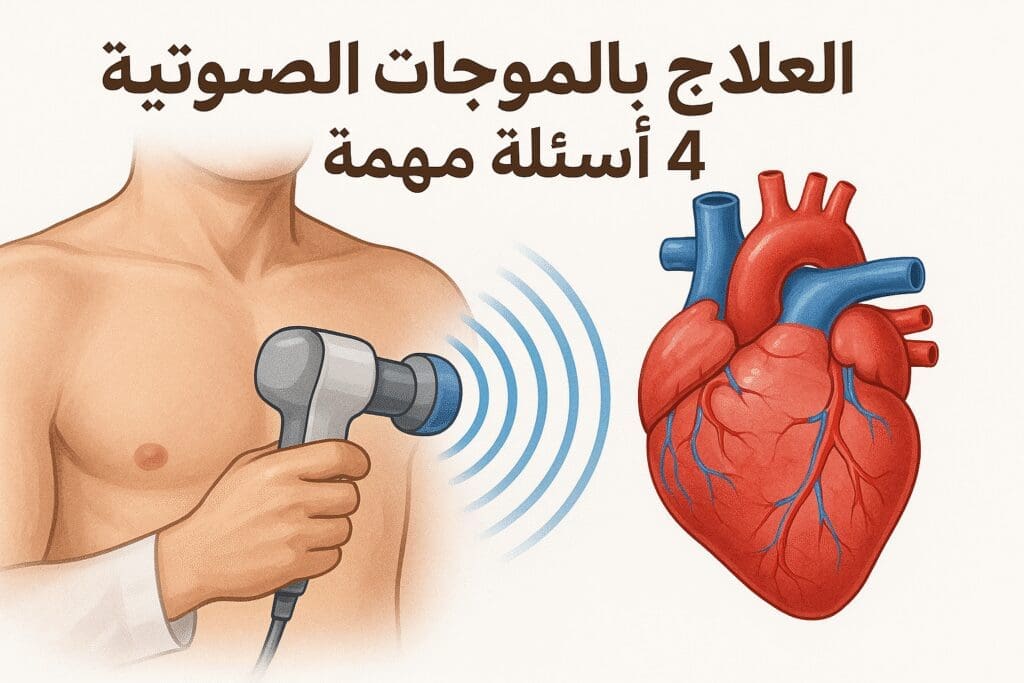

مقالات طبية من مساهمات الأطباء